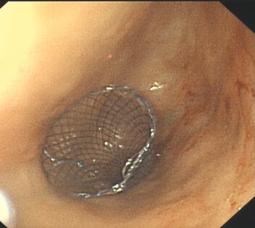

食管曲張靜脈出血套扎術(shù)

4. 食管、結(jié)腸支架置放:食道癌、結(jié)腸癌晚期失去手術(shù)機(jī)會(huì)或有手術(shù)禁忌癥者,食管氣管瘺等;